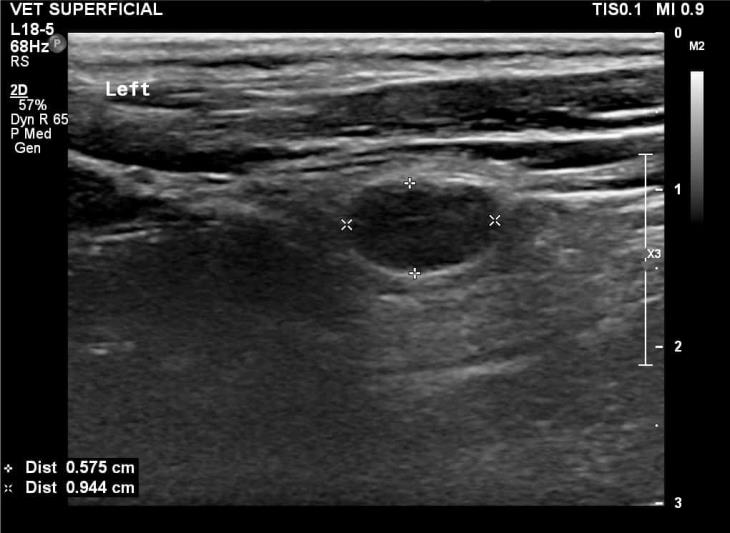

Initial diagnostic investigations revealed a large (6 x 9mm) cranial, external parathyroid nodule on the left, consistent with primary hyperparathyroidism. Archie underwent a general anaesthetic and unilateral parathyroidectomy.